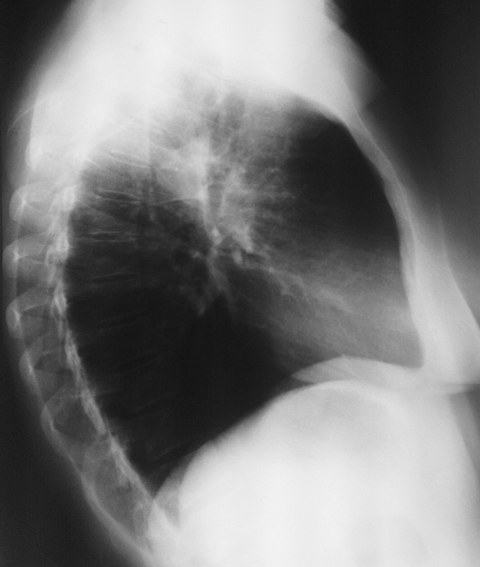

Женщина 32 года; месяц как кашляет. Повышения температутры тела не отмечала. Изначально выполнили рентгенографию. Что делать дальше?

Ок, мы определились с дифференциальным рядом при такой рентгенологической картине (Затемнение верхених сегментов правого лёгкого, S2). Какую рекоммендацию Вы бы дали такому пациенту? Что будем делать дальше?

Далее рекомендуем лабораторные исследования, КТ легких.

Давайте определимся, для начала обозначим какие КТ признаки мы видим на представленных сканах. И главное это не перечисление вариантов диагнозов (если нет однозначного варианта); а определить что надо сделать следующим этапом для достижения окончательного диагноза.

Вполне адекватная тактика. КТ контроль через 3-4 недели после антибактериальной терапии, совершенно правильно.

В данном случае, пульмонолог решил пойти на бронхоскопию; был забор материала. Лабараторный анализ (ПЦР) выявил положительную реакцию на туберкулёз.